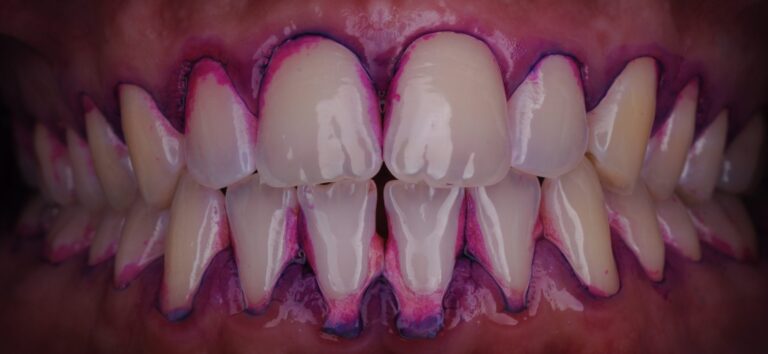

- Окрашивание налёта с помощью специального красителя:

- Визуализация налёта позволяет показать пациенту проблемные зоны.

- Цветовая индикация помогает отличить свежий налёт от старого:

- Тёмно-фиолетовый — застарелый налёт

- Светло-розовый/голубой — свежий налёт

- Это важно для мотивации и обучения: пациент наглядно видит, где недочищает.

- Удаление налёта и камня:

- Использование Airflow — мягко и эффективно удаляет биоплёнку.